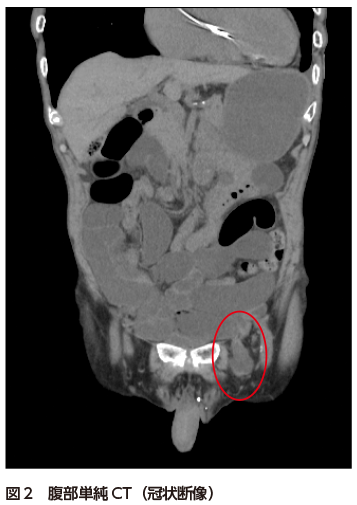

• A1:左鼠径部に小腸の脱出を認める(図12).また口側と思われる小腸および胃に拡張と内容物貯留を認める.骨盤内小腸には糞便様内容物(small bowel feces sign)を認める(掲載画像には非表示).

• A2:左大腿ヘルニアおよび小腸閉塞症.場所が類似する鼠径ヘルニアとの鑑別が重要(特に高齢女性の場合).

大腿輪は下腹壁動静脈の内側に位置しており,類似の箇所に位置する内側鼠径窩がヘルニア門となる内(直接)鼠径ヘルニアとの鑑別が重要である.男性の場合,腸管が鼠径管を通って陰嚢内へ脱出するか否かで鑑別は容易であるが,女性の場合はしばしば鑑別に苦慮する.鼠径ヘルニアはヘルニア嚢が鼠径靱帯の腹側(体表側)に,大腿ヘルニアは背側(深部側)に位置することが診断の手掛かりとなる.鼠径靱帯は横断像では同定が困難であるが,冠状断もしくは矢状断で多くの場合は同定可能であり,モニター上でスクロールしながら観察することで鼠径靱帯の同定,鼠径ヘルニアと大腿ヘルニアの鑑別がほぼ可能である4)

図1